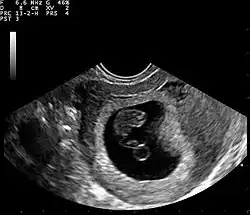

Ultrasound

Obstetric ultrasonography may also be used to detect and diagnose pregnancy. It is very common to have a positive at-home urine pregnancy test before an ultrasound. Both abdominal and vaginal ultrasound may be used, but vaginal ultrasound allows for earlier visualization of the pregnancy. With obstetric ultrasonography the gestational sac (intrauterine fluid collection) can be visualized at 4.5 to 5 weeks gestation, the yolk sac at 5 to 6 weeks gestation, and fetal pole at 5.5 to 6 weeks gestation. Ultrasound is used to diagnose multiple gestation, which cannot be diagnosed based on the presence of hCG in urine or blood.[15] Determination of the gestational age of the embryo/fetus is an additional benefit of ultrasound compared to hCG tests.[16]